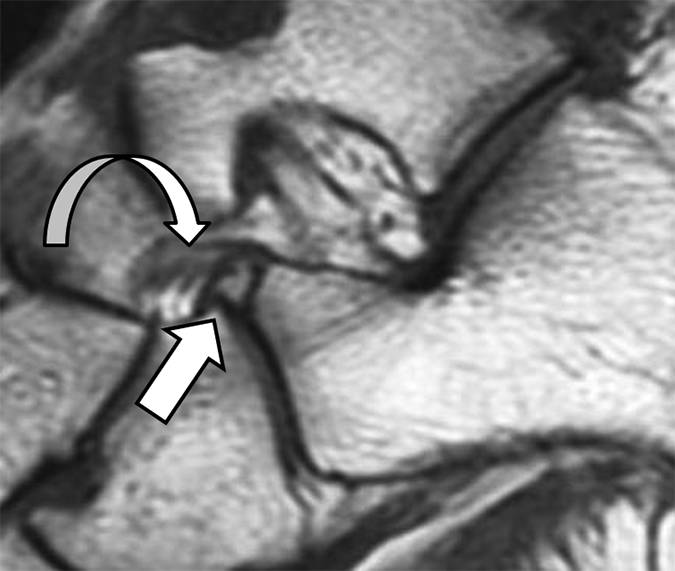

图 8A- 1型骨折与愈合2例。A,22岁的人在足球比赛期间发生骨折。 矢状T1加权MRI显示出由对应于1型骨折的前跟骨过程产生的骨片(直箭头)的小片段。 显示了分叉韧带的一部分(弯曲的箭头)。

图8B -30岁的没有创伤的男人。 脚的倾斜视图显示附属的小骨(箭头)位于跟骨,距骨,舟形和骰骨之间,近似1型前路骨折。这个小骨被称为os“calcaneus secundarius”,通过跟骨中缺乏供体位点与骨折区分。